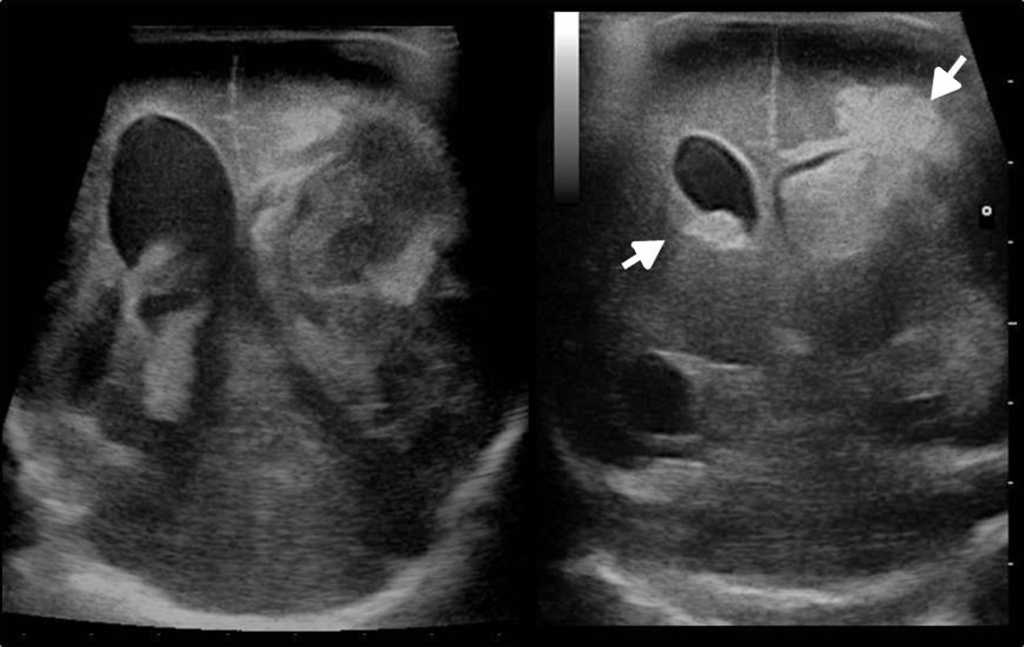

En el caso del neonato, la ecograf??a transfontanelar es de suma utilidad porque posibilita el diagn??stico de hemorragias intracraneales y la leucomalacia periventricular, las dos entidades m??s frecuentes en el prematuro (figs. 17 y 18).

A la cortesía de la Dra. Zubieta, por brindarnos las imágenes de las figuras 17 y 18.